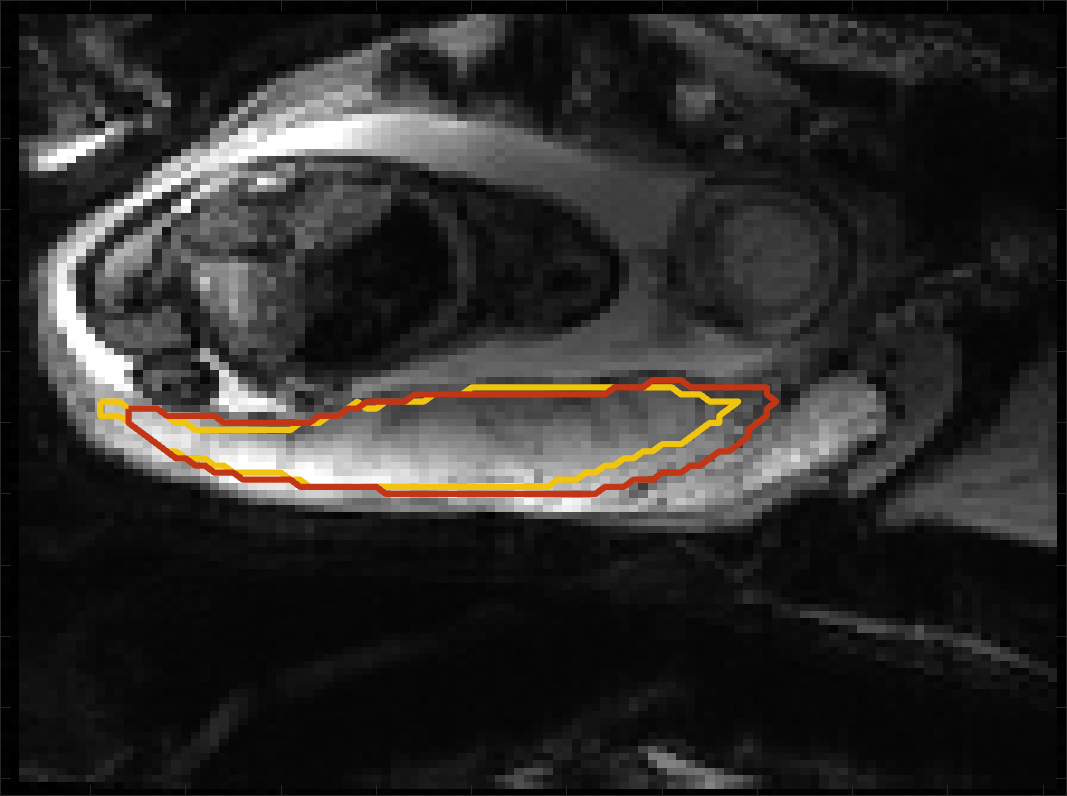

BOLD Time Series Evaluation

Figure 5 presents example predicted segmentations at multiple points in the BOLD MRI time series for subjects. The predicted segmentations are robust to large fetal deformations and placental signal changes. Figure 6 (top) presents distributions of Dice score between predicted label maps of consecutive frames in the BOLD time series for all subjects in the test set. Distributions have high medians (Dice ) for all but one case, with high density at high Dice scores (Dice ). Dice differences are highly affected by fetal and maternal motion that cause placental deformation. We visually verified that modest drops in Dice () were mainly due to fetal motion, but subjects had a small number of frames with large drops (Dice ) that were caused by errors in the produced label maps. Figure 6 (bottom) shows D models of failed segmentations from two subjects from frames with Dice . Our model omitted parts of the placenta for Subject and added a large region for Subject . In practice, these failures ocurred in a small number of frames, of frames for Subject and of frames for Subject . Overall, predicted label maps are consistent between consecutive volumes of the MRI time series, achieving a Dice of and a BOLD difference of . The small differences between the relative mean-BOLD values suggest these produced segmentations may be suitable for research studies assessing placental function.